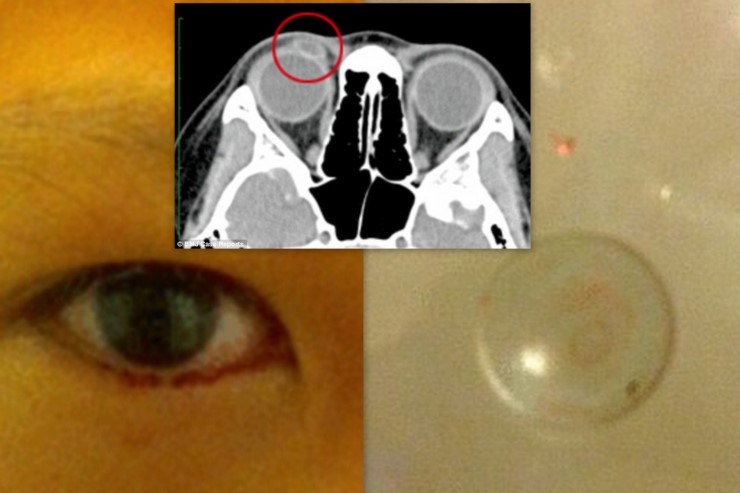

เด็กหญิงถูกส่งตัวไปรักษากับจักษุแพทย์ซึ่งต้องเข้ารับการทำ CT Scan จนกระทั่งพบว่ามีคอนแทคเลนส์ไปติดอยู่ด้านในเปลือกของเด็กหญิง ซึ่งสร้างความตกใจให้แก่แพทย์และครอบครัวอย่างมาก

ผู้เป็นแม่ของหนูน้อยระลึกขึ้นได้อีกครั้งว่านี่อาจเป็นสาเหตุที่เมื่อ 2 ปีก่อน คอนแทคเลนส์สำหรับใส่นอนเพื่อแก้ปัญหาค่าสายตาชนิดกึ่งนิ่มกึ่งแข็ง (Orthokeratology Lens ) ของเธอหายไป